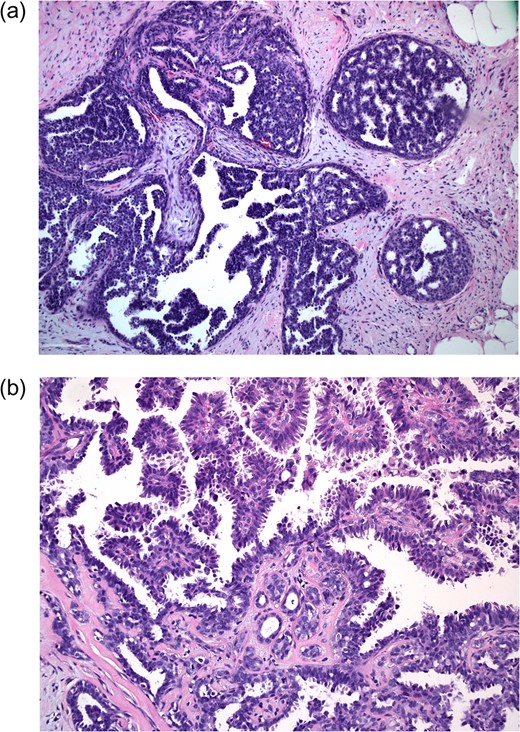

Bilateral mammogram demonstrated mild gynecomastia in both sides with no discrete mass or clusters of microcalcifications (Fig. 1). A follow-up ultrasound around the area of palpable concern did show a prominent duct with irregular contours at the 6:00 position in the left breast (Fig. 2). Excisional biopsy was recommended and a subareolar biopsy of the left breast was performed.

Ultrasound of the left breast at the 6:00 region reveals a mildly hypoechoic mass with ductal extension.